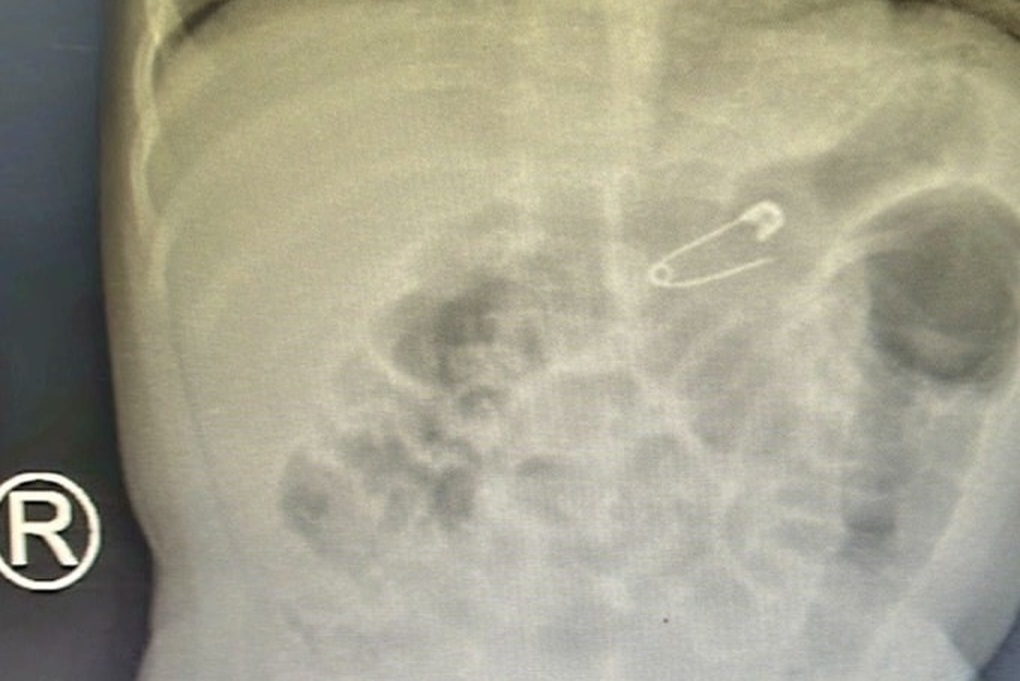

Dị vật là chiếc kim băng sắc nhọn được phát hiện qua ảnh chụp phim (Ảnh: Bệnh viện cung cấp).

Tại bệnh viện, kết quả chụp X-quang ngực thẳng nghiêng phát hiện dị vật hình kim băng (diện tích 1,5 x1 cm) mắc tại khu vực dạ dày bệnh nhi.